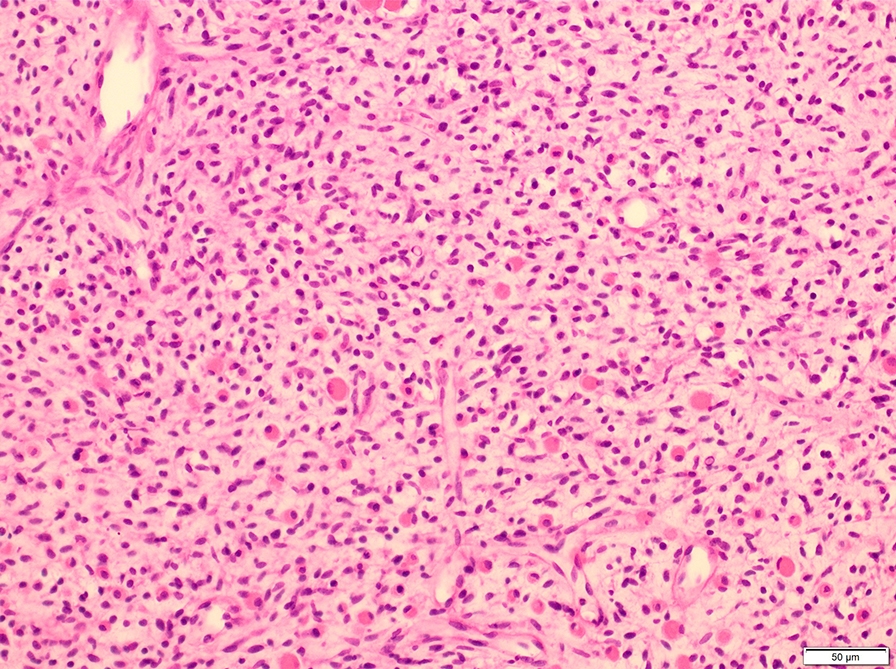

Microscopic (histologic) description

- Composed of primitive mesenchymal cells that show variable degrees of skeletal muscle differentiation

- They are moderately cellular but in the typical pattern often contain both hypocellularity and hypercellular areas with a loose, myxoid stroma

- Perivascular condensations of tumor cells in the less cellular regions are common

- Sheets of small, stellate, spindled or round cells with scant or deeply eosinophilic cytoplasm and eccentric, small oval nuclei with a light chromatin pattern and inconspicuous nucleoli

- Can occasionally identify tumor cells that contain generous amounts of eosinophilic cytoplasm, a feature of rhabdomyoblastic differentiation (so called strap cells)

- These may become more prominent with chemotherapy (chemotherapeutic induced cytodifferentiation)

- May have cells with elongated tails of cytoplasm (tadpole cells)

- If densely cellular, may resemble solid alveolar rhabdomyosarcoma (Am J Clin Pathol 2013;140:82)

- Botryoid variant frequently shows a cambium layer: a hypercellular zone immediately beneath the epithelial surface

- Cells are undifferentiated, round or spindled with minimal cytoplasm, frequent mitotic figures

- Deeper layers of the tumor are typically less cellular but overall conform to the histology of embryonal rhabdomyosarcoma (ERMS) with variation by region

Microscopic (histologic) images

Contributed by Erdener Özer, M.D., Ph.D. and Mark R. Wick, M.D.

Contributed by Carolina Martinez Ciarpaglini, M.D., Ph.D. (Case #276) - tonsillar mass